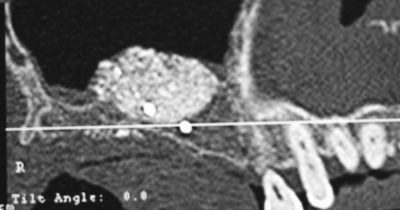

Les photos qui illustrent le texte ont pour unique objectif de vous aider à mieux comprendre les techniques utilisées. Elles correspondent chacune à une réalité qui ne peut être transposée car chaque situation clinique est différente et unique.

L’intervention chirurgicale consiste en une reconstruction osseuse du maxillaire ou de la mandibule avant la mise en place des implants dentaires par votre chirurgien.